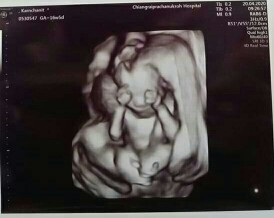

ส่วนตัว กำหนดคลอด วันที่ 30 ก.ย. 63 ตอนนี้อายุครรภ์ 16 สัปดาห์ 6 วัน เมื่อวานหมอนัดตรวจคัดกรองดาวน์ซินโดรม อัลตร้าซาวน์เห็นเพศลูกแล้ว ตื่นเต้น ดีใจมากค่ะ ไม่คิดว่าจะเห็นเพศไวแบบนี้ ก่อนหน้านี้คิดว่า 20 สัปดาห์ ถึงจะเห็นเพศ แม่แม่คนไหนกำหนดคลอดเดือนกันยายนเหมือนกันบ้างคะ? อยากเห็นทีมกันยายนค่ะ ^^